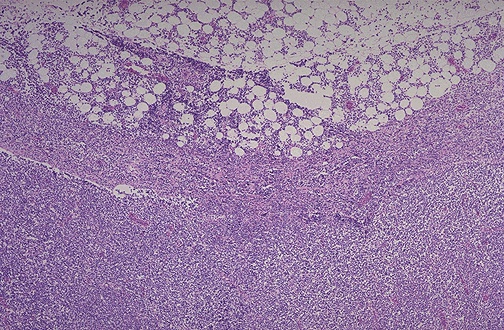

| This pattern of malignant lymphoma is diffuse and no lymphoid follicles are identified. Under low power, note that the normal architecture of the lymph node is obliterated. The lymph node is replaced by an infiltrate of small (mature-appearing) neoplastic lymphocytes, and the infiltrate extends through the capsule of the lymph node and into the surrounding fat. The diagnosis is: malignant lymphoma, small lymphocytic type, diffuse (also known as: "well-differentiated" lymphocytic lymphoma). |